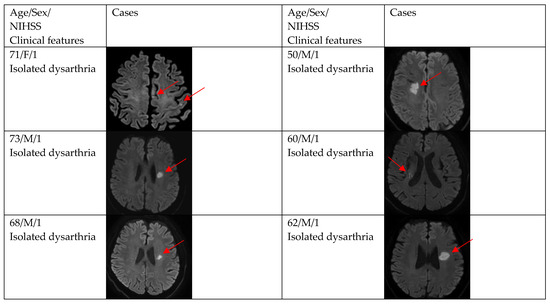

| DWI positivity | 12 (66.7) | 29 (87.9) | 0.154 |

| Single and small lesion | 10 (83.3) | 16 (55.2) | |

| Multiple or territorial lesions | 2 (16.7) | 13 (44.8) | |